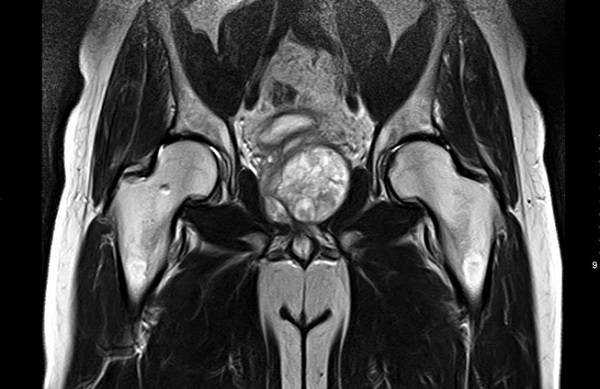

Магнитно-резонансное сканирование тазобедренных суставов